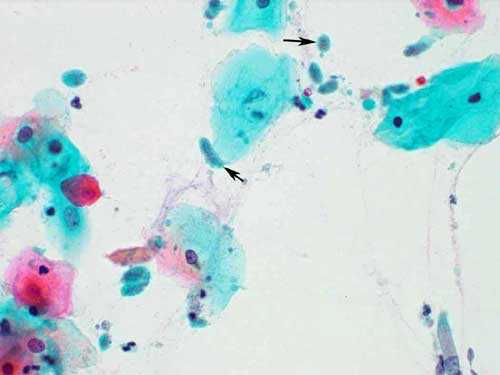

trich2